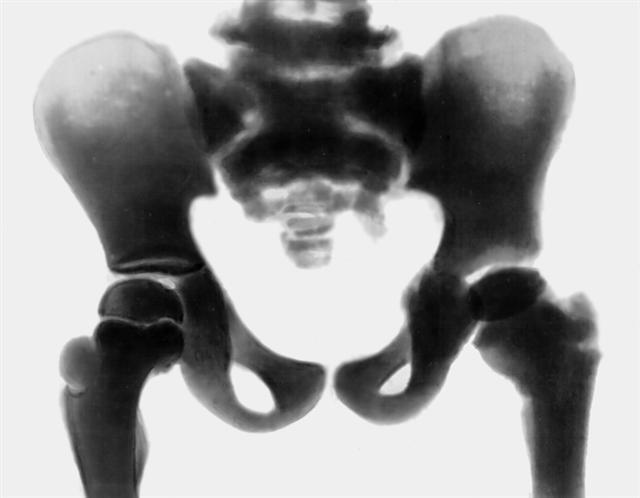

Рис. а). Рентгенограмма костей таза при врожденной мраморной болезни: избыточное развитие компактного вещества, очаги склерозирования костной ткани и уплотнение ее структуры в различных костях скелета.